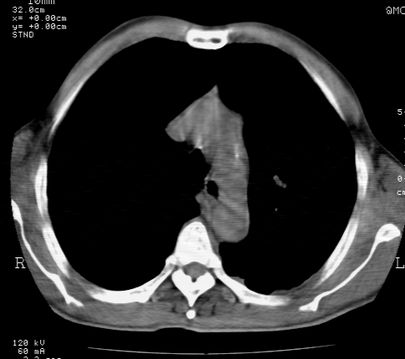

左肺门肿块,相应支气管闭塞,左肺上叶、舌叶大片及散在高密度影,部分呈不张改变,两肺纹粗乱,左侧胸腔积液。考虑左侧中央型肺癌伴阻塞性改变。

左肺门见巨大软组织肿块影,直径约--,境界清,左上肺叶支气管变窄,左上肺舌叶见大片状密实影,余肺纹理增多、紊乱、纤细、部分网格状,两肺透亮度增高,纵隔内见增大多发淋巴结影,心影略左偏,左侧少量胸腔积液。

左侧中央型肺癌伴左上肺舌叶不张、纵隔淋巴结转移,左侧少量胸腔积液。